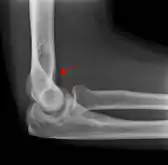

علامة الوسادة الدهنية (بالإنجليزية: Fat pad sign) أو علامة الشراع (بالإنجليزية: Sail sign) هي علامة طبية تظهر في الأشعة المقطعية وتشير إلى كسر عظم مخفي. شكلة على شكل شراع.[1] سبب هذه العلامة هو إزاحة الوسادة الدهنية المحيطة بمفصل المرفق. قد تظهر علامة أمامية أو علامة خلفية أو تظهر كلتا العلامتين.

تظهر علامة الوسادة الدهنية الخلفية في حالة الكسر اللقمي لعظم العضد. أما عند البالغين، فتظهر في حالة كسر رأس الكعبرة. تحدث علامة الوسادة الدهنية في الكسور التي تحدث داخل المفاصل فقط.

يمكن ضغط الوسادة الدهنية الخلفية في الحفرة الزجية بواسطة الضغط على وتر العضلة ثلاثية الرؤوس العضدية، وبذا ستكون غير مرئية لتصوير جانبي للمرفق بالأشعة.[3] عندما يكون هناك كسر في طرف عظم العضد أو وجود أي مرض يصيب المرفق أو التهاب يحدث حول الغشاء الزليلي، فهذه ستزيح الوسادة الدهنية عن مكانها الطبيعي. تعد علامة الوسادة الدهنية الخلفية العلامة الواضحة الوحيدة لكسر، ولا سيما عند الأطفال.

كسر رأس الكعبرة تظهر فيه علامة الوسادة الدهنية